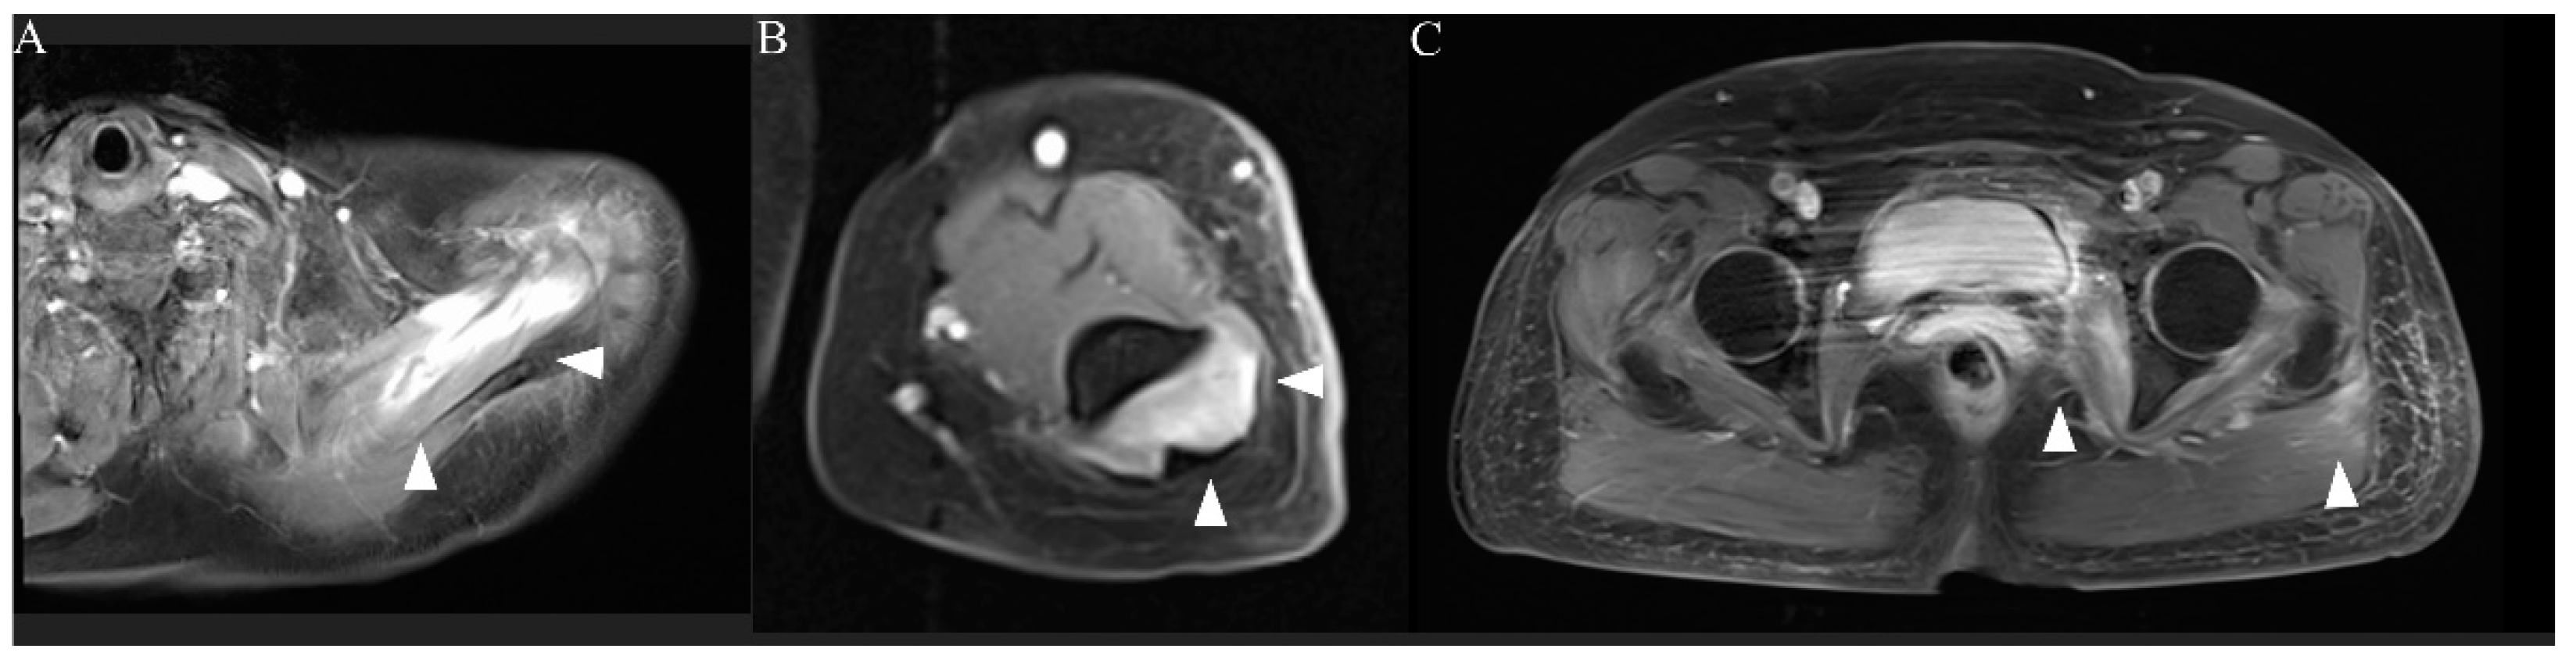

The patient was admitted and treated with intravenous normal saline for rhabdomyolysis and loxoprofen for myalgia. On day 3 of hospitalization, her weakness and myalgia had completely disappeared. However, the next day, follow-up MRI showed slight exacerbation of the hyperintensity of the left upper limb muscles and attenuation of the hyperintensities of the lower limb muscles (Figure 2D–F). Most affected muscles were enhanced, and only the left supraspinatus muscle had homogeneous enhancement (Figure 3A–C). On day 5 of hospitalization, weakness of the left supraspinatus and deltoid muscles (MRC scale 5/4) developed, with swelling and tenderness of the left supraspinatus. A nerve conduction study (NCS) showed that the compound muscle action potentials (CMAP) of the right and left deltoid muscles were 9.210 and 2.540 mV, respectively. MRI on day 8 of hospitalization showed attenuation of the hyperintensity of all muscles. The weakness gradually subsided and then disappeared on day 10 of hospitalization. Electrolytes and renal function were within normal limits during hospitalization. CK, myoglobin, and liver enzyme concentrations improved over the course of hospitalization, and the CK concentration returned to normal on day 10 of hospitalization. The patient was discharged the next day.

Figure 3.

MRI of the extremities (post-contrast T1 images). Only the left supraspinatus muscle was homogeneously enhanced ((A), arrowheads). Other affected muscles showed enhancement centered on the rim ((B,C), arrowheads).